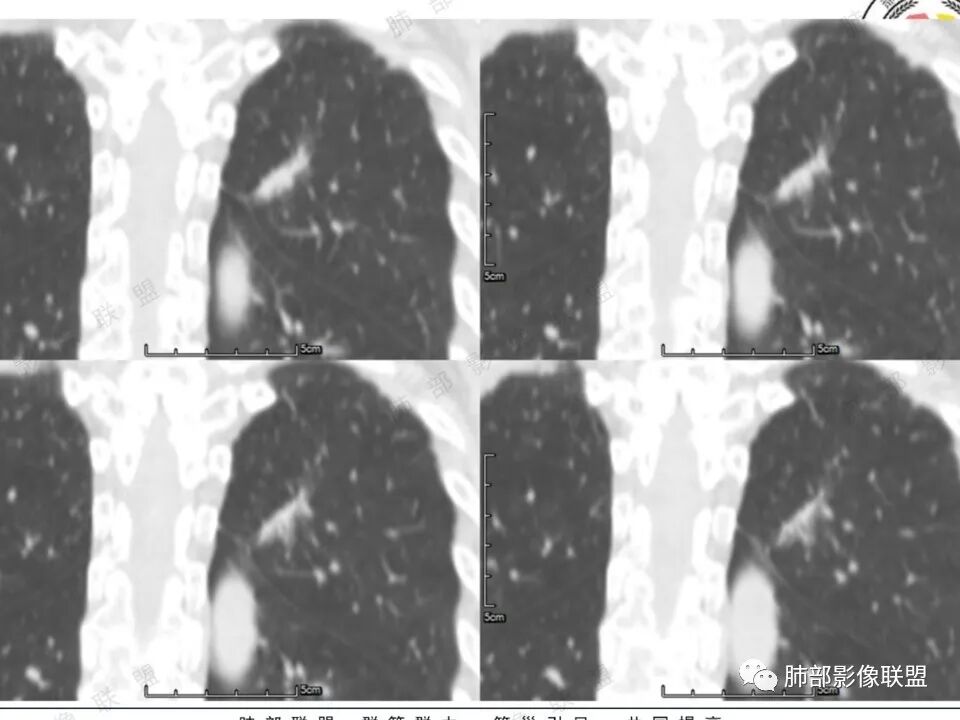

高强化,实性结节,边缘有磨玻璃,有膨隆,斜裂侧偏平直胸膜凹陷,IAC,鉴别炎性肉芽肿

左肺上叶长条状病灶,胸膜牵拉,边缘平直,磨玻璃边界清楚,不均匀强化,考虑炎性,不完全排除肺癌

左肺结节,形态不规则,边缘略收缩,分叶,部分边缘平直,周围可见清晰磨玻璃影,增强后明显强化,考虑:血管瘤,炎性假瘤,鉴别腺癌

左肺上叶尖后段病灶,毛玻璃边界不清,实性成分边缘平直,重建,病灶长条形,增强明显强化,考虑炎症

中年女,左肺结节,边缘平直,明显持续不均匀强化,周围略毛糙,考虑IMT

左肺结节,形态不规则,磨玻璃边界欠清,增强明显强化,考虑炎性,OP?IMT?,鉴别腺癌

中年女性,左肺上叶长条状病灶,宽基底与胸膜交界,胸膜凹陷,病灶边缘平直,局部收缩及膨隆,周围可见磨玻璃,其边界清楚,增强病灶不均匀强化,影像表现有炎性病变,也有明显占位表现,考虑OP,有膨胀性表现的小结节,不完全排除肺癌!需要结合相关检查。

混合磨玻璃,边界清,边缘凹陷,月牙铲,虽明显强化,还是先考虑腺癌,鉴别炎性肉芽肿或IMT等。

晨读:中年女性,体检发现,左肺上叶结节,形态不规则,呈长条状,分叶,部分边缘平直,周围可见磨玻璃影,增强后明显强化,首先考虑良性病变:1、炎性病变。2、血管瘤。

体检发现左肺上叶尖后段混合磨玻璃结节,考虑浸润性腺癌可能性大,建议抗感染后复查,明显强化有不支持的地方,左肺上叶尖后段外侧胸膜下小磨玻璃结节,提示AAH。

女,41岁,体检发现肺部结节。左肺上叶长形病灶,具有轻度膨胧感,刀切尖角征,胸膜粘连,早期强化见薄环强化征象,后期有延迟强化特点。病灶周围不是很干净。考虑结核肉芽肿或炎症肉芽肿。

中年女性,查体发现左上肺条块结节,靠近斜裂,边缘平直有收缩,胸膜牵拉,明显强化,考虑炎性假瘤或炎性肉芽肿,鉴别腺癌。

中年女性,体检发现。左肺上叶后段不规则结节灶,密度不均匀,病灶周围可以边界似清非清毛玻璃影,临近胸膜牵拉,增强扫描病灶明显不均匀强化。考虑炎性假瘤,鉴别腺癌。

混合磨玻璃,边界清,分叶,收缩力强,月牙铲,胸膜凹陷,虽明显强化,还是先考虑腺癌,鉴别炎性肉芽肿。

左肺上叶尖后段实性结节,边缘有清晰磨玻璃,胸膜有牵拉凹陷,明显强化,CT值超过主动脉,考虑血管畸形(周围磨玻璃可能是出血),鉴别IAC(影像表现符合,强化不符)

混合密度结节,磨玻璃密度边缘清楚,考虑腺癌。

患者中年女性,体检发现。胸部CT:左肺上叶后段长条形结节灶,边缘光滑,边界清楚,见分叶、毛刺、胸膜牵拉及平直征象。增强明显强化,内可见血管增粗,综合考虑恶性病变,浸润性腺癌可能大,鉴别结核。

形态特征符合腺癌,就是这个强化幅值相对少见些,肺内其他高强化病变如类癌、血管瘤等形态又不甚符合。还是常规考虑浸润腺癌吧,当然抗炎复查这个过程还是要的。

41岁女性,左肺上叶不规则结节,边缘见似清非清的磨玻璃影,叶间裂牵拉。整体病灶边缘平直,强化明显。另左上叶外侧尚有一磨玻璃结节(蘑菇兄弟?),考虑炎性肉芽肿可能性大。强化太明显让人很纠结,会不会存在CD,但边缘又有磨玻璃影;腺癌、结核、隐球都没有见过强化这么明显的,强化程度与主动脉基本一致,不会是动静脉畸形吧。

左上肺前后段不规则实性病灶,浅分叶,边缘部分平直收缩,轻微胸膜牵拉,伴周围磨玻璃样改变,强化明显,感觉是炎性恶性征像均有。

左肺上叶后段条片状影,边缘部分模糊,前缘平直后缘澎隆,周围可见大部分清晰的GGO,毛刺不明显,可见索条影,内密度不均可见条状低密度,增强除条状低密度外明显强化。支气管似见病灶边缘截断。考虑腺癌可能,抗炎治疗除外炎性肉芽肿。

强化太猛,血管畸形?边缘磨玻璃区,腺癌?

1.中年女性,体检发现;2.左肺上叶后段长条形结节灶,边缘有膨隆,也有收缩,腺癌和炎性结节都可以,但是周围见边界清楚磨玻璃影强烈提示腺癌可能性。3.显著强化的肺结节,无论如何都应当引起我们的高度重视!尽管炎性病灶和新生物都可以,尽管强化程度不能作为诊断癌肿的依据。

4.本例结节强化程度明显低于主动脉,也缺乏血管畸形的典型的迂曲结构,血管畸形可能性不大。

★存在边界清楚的磨玻璃影,常常提示腺癌的可能性,尤其随诊复查没有变化。